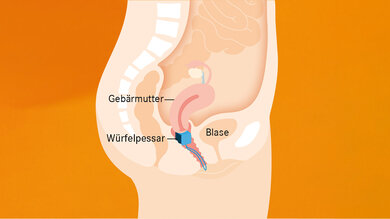

Pessare sind medizinische Hilfsmittel. Sie werden in die Vagina eingeführt und stützen von innen Blase und Harnröhre. Gleichzeitig wird die Harnröhre leicht an das Schambein gedrängt. So verhindern Pessare, dass aus Versehen Urin austritt. Durch die Stützfunktion helfen sie bei Beckenbodenproblemen nach einer Geburt, bei einer Gebärmutter- oder Blasensenkung. Allerdings beheben sie nur das Problem, nicht die Ursache – nämlich die fehlende Stütze durch kräftige Beckenbodenmuskeln und Bindegewebe. Zwar regen Pessare selbst ein wenig die Muskeln an, zusätzlich sollte aber ein Beckenbodentraining erfolgen.

Beim Einsetzen des Pessars am besten ein Bein auf Bett oder Badewanne abstellen. Gleit- oder Östrogengele erleichtern das Einführen zusätzlich. Lassen Sie sich von Ihrem Arzt oder Ihrer Ärztin erklären, an welcher Stelle das Pessar genau sitzen soll. Nach dem Einsetzen sollte es nicht drücken. Bei korrektem Sitz spüren die Frauen während des Tragens kaum etwas. Würfelpessare verfügen über einen fest verankerten Rückholfaden, bei den anderen Pessaren hakt man den Finger in den Ring oder zieht an der Glocke. Wichtig: vor und nach dem Einsetzen und Entfernen Hände waschen.

Üblicherweise sitzen Pessare vor dem Muttermund. Sie lassen sich wie ein Tampon einführen